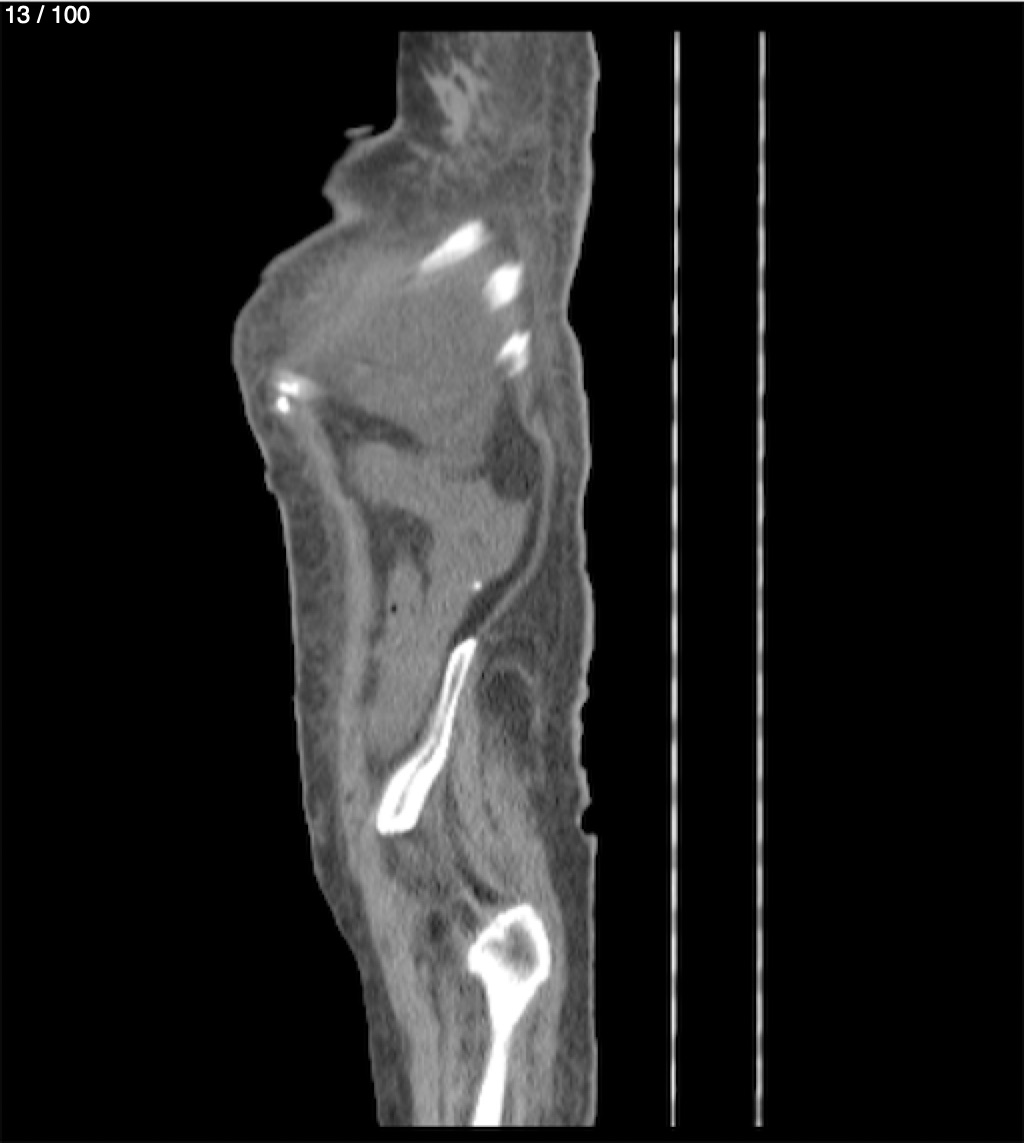

Hilda Geronimo Mendez 60A - T.C Abdomen Simple